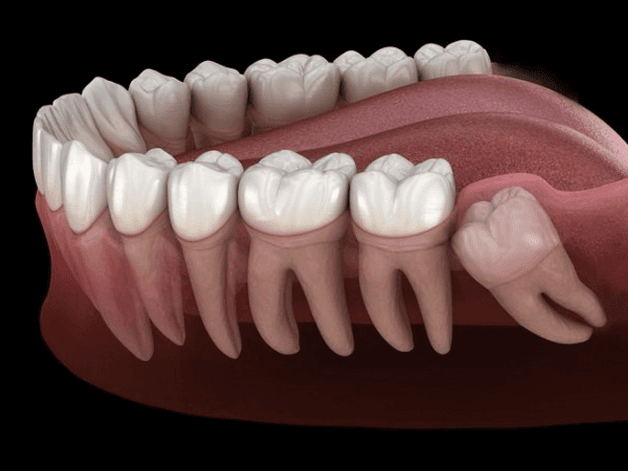

Răng khôn trong giai đoạn bắt đầu mọc sẽ cần đâm xuyên qua nướu. Do vậy, những người mọc răng khôn sẽ phải trải qua cơn đau dữ dội. Ngoài ra, răng khôn là răng hàm mọc trong cùng và sau cùng. Vậy nên, việc răng không có đủ chỗ mọc là điều dễ xảy ra. Từ đó, răng sẽ dễ bị mọc chen lấn, chèn ép các răng bên cạnh.

Tình trạng răng khôn mọc lệch sẽ khiến răng đâm vào phần răng bên cạnh. Từ đó dẫn tới tiêu ngót chân răng và thoái hóa trở thành u nang. Những u nang bệnh lý này nằm trong xương hàm nếu không được điều trị đúng cách sẽ ngày càng phát triển. Chúng có thể gây hỏng răng, hỏng xương hàm của người bệnh.